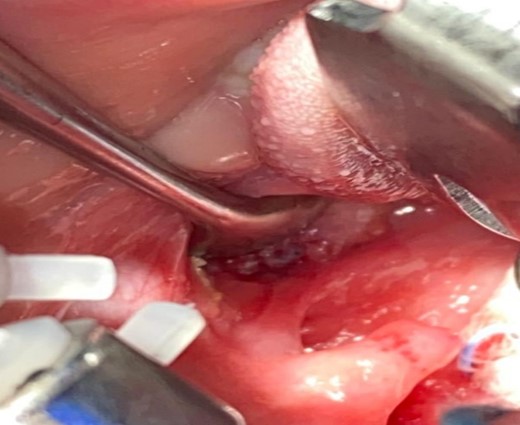

After draping and sterilisation, the small left-sided neck punctum was identified, probing of the fistula tract by a lacrimal probe was done, followed by the insertion of an arterial catheter inside the fistula tract (Fig. 6). The amount of methylene blue added was 0.01 ml per 2 ml of fibrin glue, and a total of 4 ml of this mixture was injected. This mixture allows the glue to be dyed adequately and does not inhibit its solidification. The arterial catheter was totally inserted, about 7 cm in length, and injection of methylene blue with fibrin glue was performed using an arterial catheter inside the tract. An elliptical incision was made around the fistula opening, followed by dissection of the tract. The tract was obvious, firm and colored with methylene blue. The tract was easily dissected without the need to remove extra tissues around it. Another superior incision, a step ladder incision, was made as the tract was long. The tract followed to its entry into the tonsillar fossa, which was ligated. The internal carotid artery, internal jugular vein, hypoglossal nerve and glossopharyngeal nerve were all identified and preserved. Bilateral tonsillectomy was performed, and the tract was visualised within the left tonsil (Figs 1–4). The left tract at the tonsillar bed after the tonsillectomy was ligated and cauterised. Then bilateral auricular sinus excision is done. The patient was then seen after 3 months of surgery and was doing well.

Left tonsil with clear intraoral fistula opening colored by methylene blue with fibrin before removal.